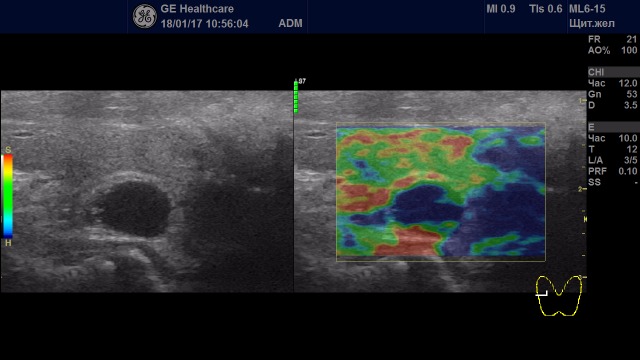

Образования с неудовлетворительной эластичностью (тип IV-V)